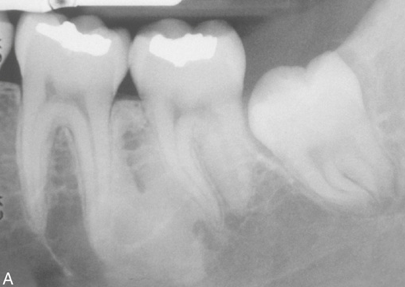

What is the likely Dx?

Idiopathic osteosclerosis. NOTE he said this will be a CPC.

Couple of notes for Idiopathic osteosclerosis.

Do not confuse with condensing osteitis which is associated with an infection.

Do not confuse with focal cemento-osseous dysplasia which will have a radiolucent rim.

Do no confuse with cementoblastoma which will be fused with the tooth.